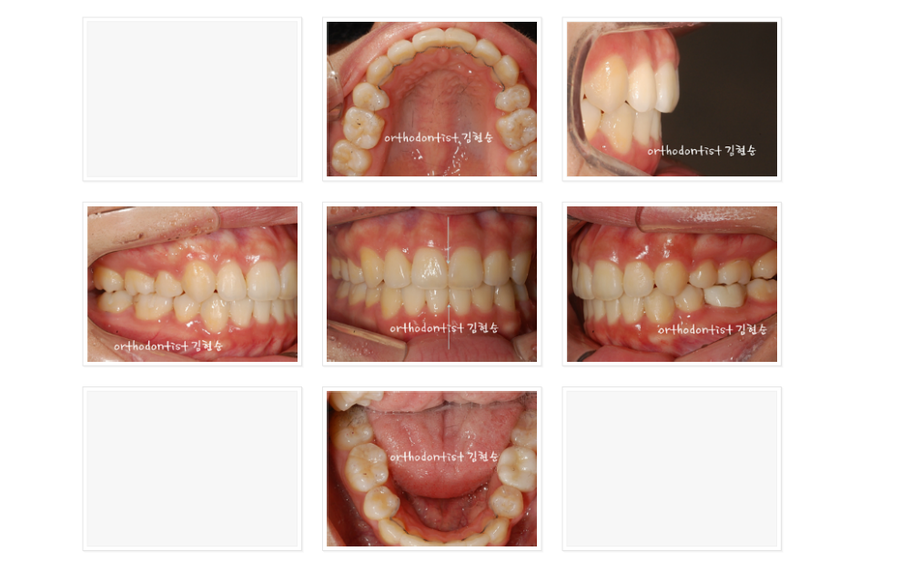

비교해 보겠습니다.

사진상으로도

얼굴모습의 변화가 매우

뚜렷한 경우입니다.

- 교정전에는 심미선 밖으로

뚜렷히 돌출되어 있던 입이

심미선 위로 놓였습니다.

- 무턱 증상을 보이던

턱선이 살아났습니다.

- 또한 돌출입 개선으로

입이 들어가면서

외려 코가 높아보이는,

긍정적인 부수적 효과인

자연스러운 성형 느낌도

얻게 되었습니다.

- 기능적인 관점에서

위아래 사진을 보시면돌출입 교정 전

문제가 되었던 치열 문제가

완전히 해결되었습니다.

6. 치열 문제가 해결되니

어긋나있던 치아 중심선도

바로 잡혔습니다.^^